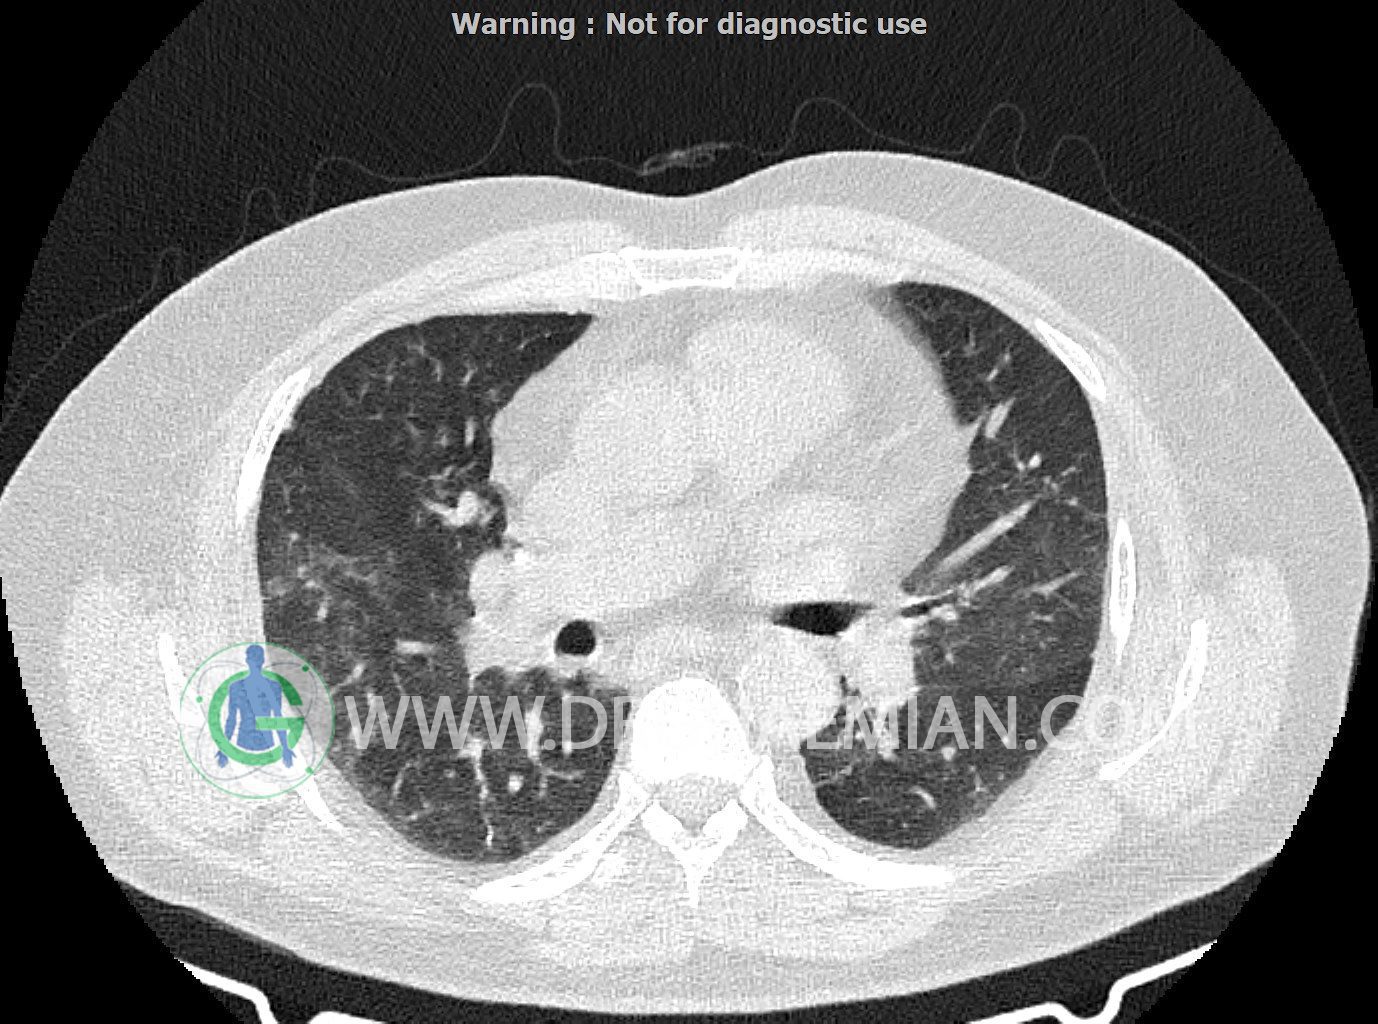

سی تی اسکن ریه یک روش تصویربرداری است که با استفاده از تشعشعات تصاویر عرضی مقطعی از ریه و بالا تنه ایجاد می کند. در این کیس کاردیومگالی،باندهای آتلکتازی و فیبروتیک پراکنده،کدورت های گراند گلاس،زمینه ی ادم قلبی (مراحل اولیه)،مشهده میشود.

در سی تی اسکن اسپیرال ریه ها و مدیاستن بدون کنتراست وریدی (مولتی دیدکتور 16 با مقاطع ظریف و بازسازی کرونال):

کاردیومگالی

باندهای آتلکتازی و فیبروتیک پراکنده در دو طرف

smooth septal thickening در لوب فوقانی ریه ها

peribronchial wall-thickening و عروق prominant در هیلوم دو طرف و کدورت های گراند گلاس دو طرفه

مشهود است.

شواهد فوق در درجه اول می تواند در زمینه ی ادم قلبی (مراحل اولیه) باشد.